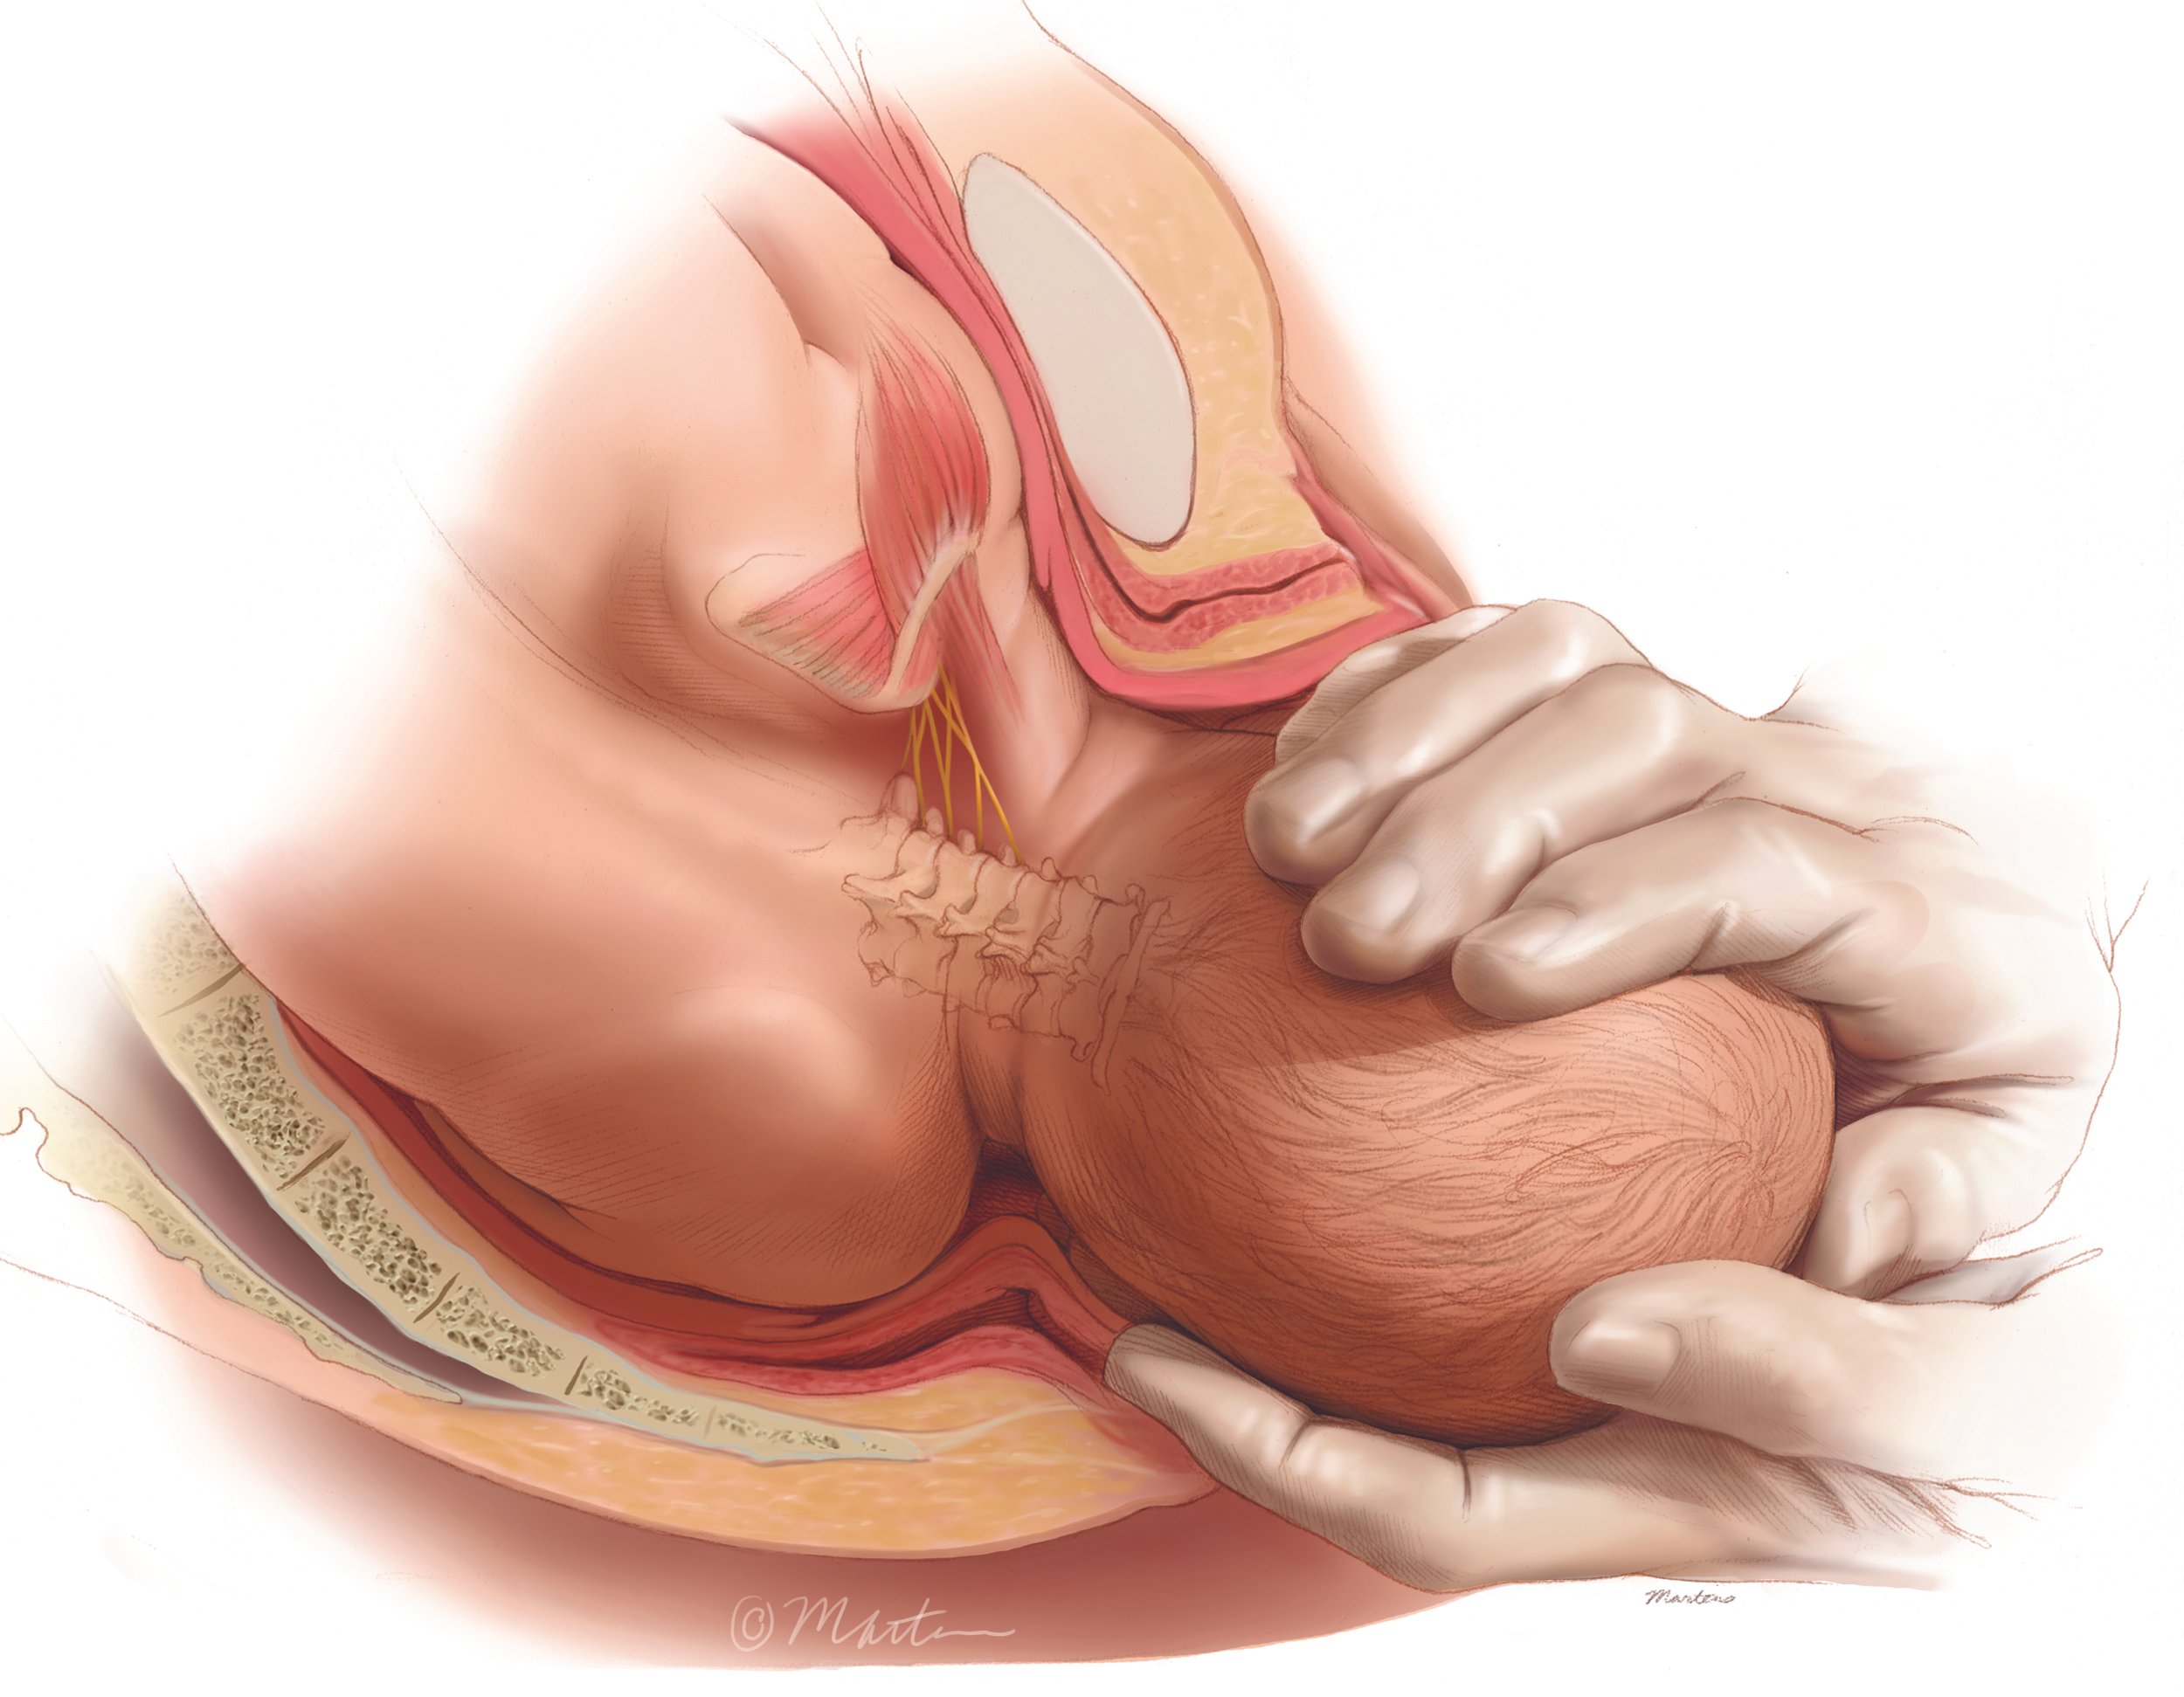

Difficult Cesarean Push Technique

Shoulder Dystocia